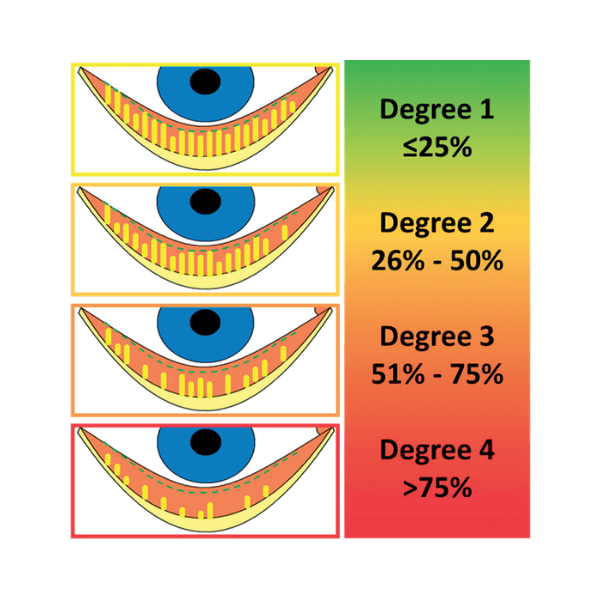

Meibomask® provides customized treatments based on the MGD severity level detected with Me-check® screening instrument. According to severity of meibomian glands loss, Meibomask® releases the correct amount of energy and treatment duration for the specific patient.